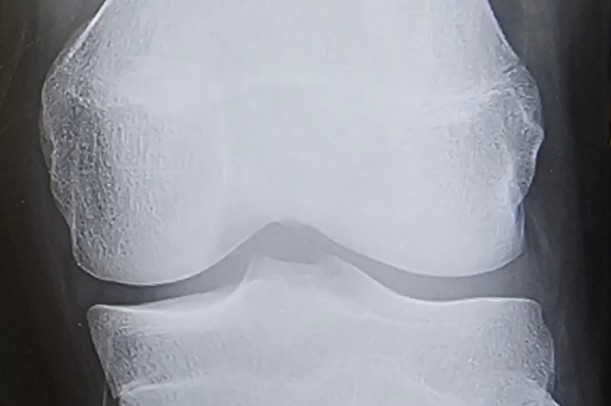

背が伸びるとは、実は骨の端にある「骨端線(こったんせん)」という軟骨部分が伸びていくことを指します。

骨端線は、骨と骨の間にある軟骨の層で、そこに新しい骨組織が少しずつ形成されていくことで身長が伸びていきます。